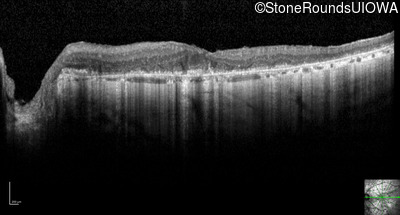

Optical Coherence Tomography - Right - 20/25 -1

Exemplar / OCT Stack